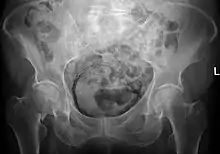

![]() | |

| Regulation of urine production by ADH and aldosterone | |